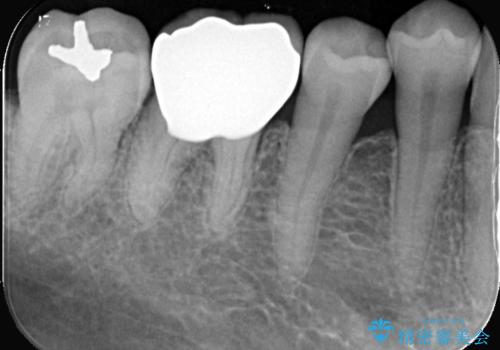

- 「銀歯を白くしたい」を主訴に来院された患者様です。銀歯を外し虫歯を除去後、オールセラミッククラウンで治療を行いました。

銀歯を外して内部の虫歯を丁寧に除去した後、オールセラミッククラウンにて修復を行いました。審美性と機能性の両面で改善が得られ、患者様にもご満足いただきました。